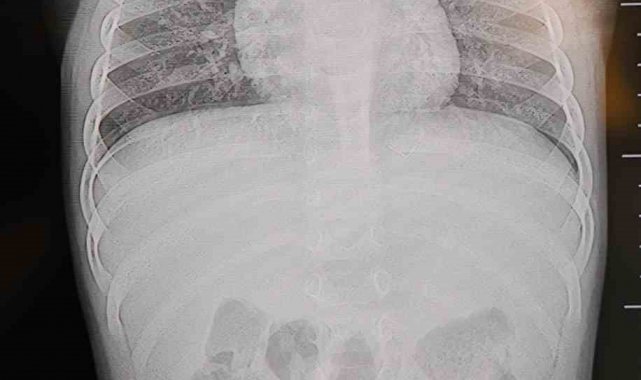

Alınan bilgiye göre, Kahramanmaraş'ta farklı ortopedi, çocuk cerrahisi ve beyin cerrahisi kliniklerine başvurusu yapılan bir yaşındaki bebeğin, sırt bölgesinde yabancı bir cisim olduğu ancak müdahalenin zor olduğu ve 8 yaşına kadar beklenmesi gerektiği bildirildi. Aile, bebekleri için son olarak HG Hospital'e başvurdu. HG Hospital Beyin ve Sinir Cerrahisi Uzmanı Prof. Dr. İdris Altun tarafından yapılan tetkiklerde, yabancı cismin cilt altında, omurilik kanalına yakın bir bölgede olduğu ve akciğer zarına doğru ilerlediği belirlendi. Hasta, genel anesteziye alınmadan, lokal anestezi ve sedasyon eşliğinde ameliyata alındı. Yapılan müdahalede yabancı cisim tamamen çıkarıldı. Çıkarılan cismin, ince zımba teline benzer metal bir tel olduğu ve yaklaşık 2 santimetre uzunluğunda bulunduğu tespit edildi. Hasta, aynı gün taburcu edildi.

Konuya ilişkin açıklama yapan Prof. Dr. İdris Altun, "Sırtında yabancı bir cisim olduğu söylenmiş ancak çıkarılamayacağı ve 8 yaşına kadar beklenmesi gerektiği ifade edilmişti. Bize başvurduğunda yaptığımız tetkiklerde, cilt altında, omurilik kanalına çok yakın ve akciğer zarına doğru ilerleyen bir yabancı cisim tespit ettik. Hastamızı tamamen uyutmadan, lokal anestezi ve sedasyon eşliğinde müdahale ederek lezyonu tamamen çıkardık. Çıkardığımız cismin ince zımba teline benzer, yaklaşık 2 santimetre uzunluğunda metal bir tel olduğunu gördük. Bu yabancı cisim alınmasaydı, bölgede enfeksiyon gelişebilirdi. Enfeksiyon sonucu omurilik kanalında ciddi hasarlar oluşabilir, çocuk büyüdükçe cismin hareket etmesine bağlı olarak omurilikte zedelenmeler meydana gelebilirdi. Ayrıca yana doğru ilerleyerek akciğer zarına ve akciğere batma riski vardı. Bu da enfeksiyona ve ilerleyen süreçte tümörle karışabilecek tablolara neden olabilirdi. Şu an hastamız gayet sağlıklı. Gerekli kontrolleri yaptık ve aynı gün taburcu ettik" dedi.